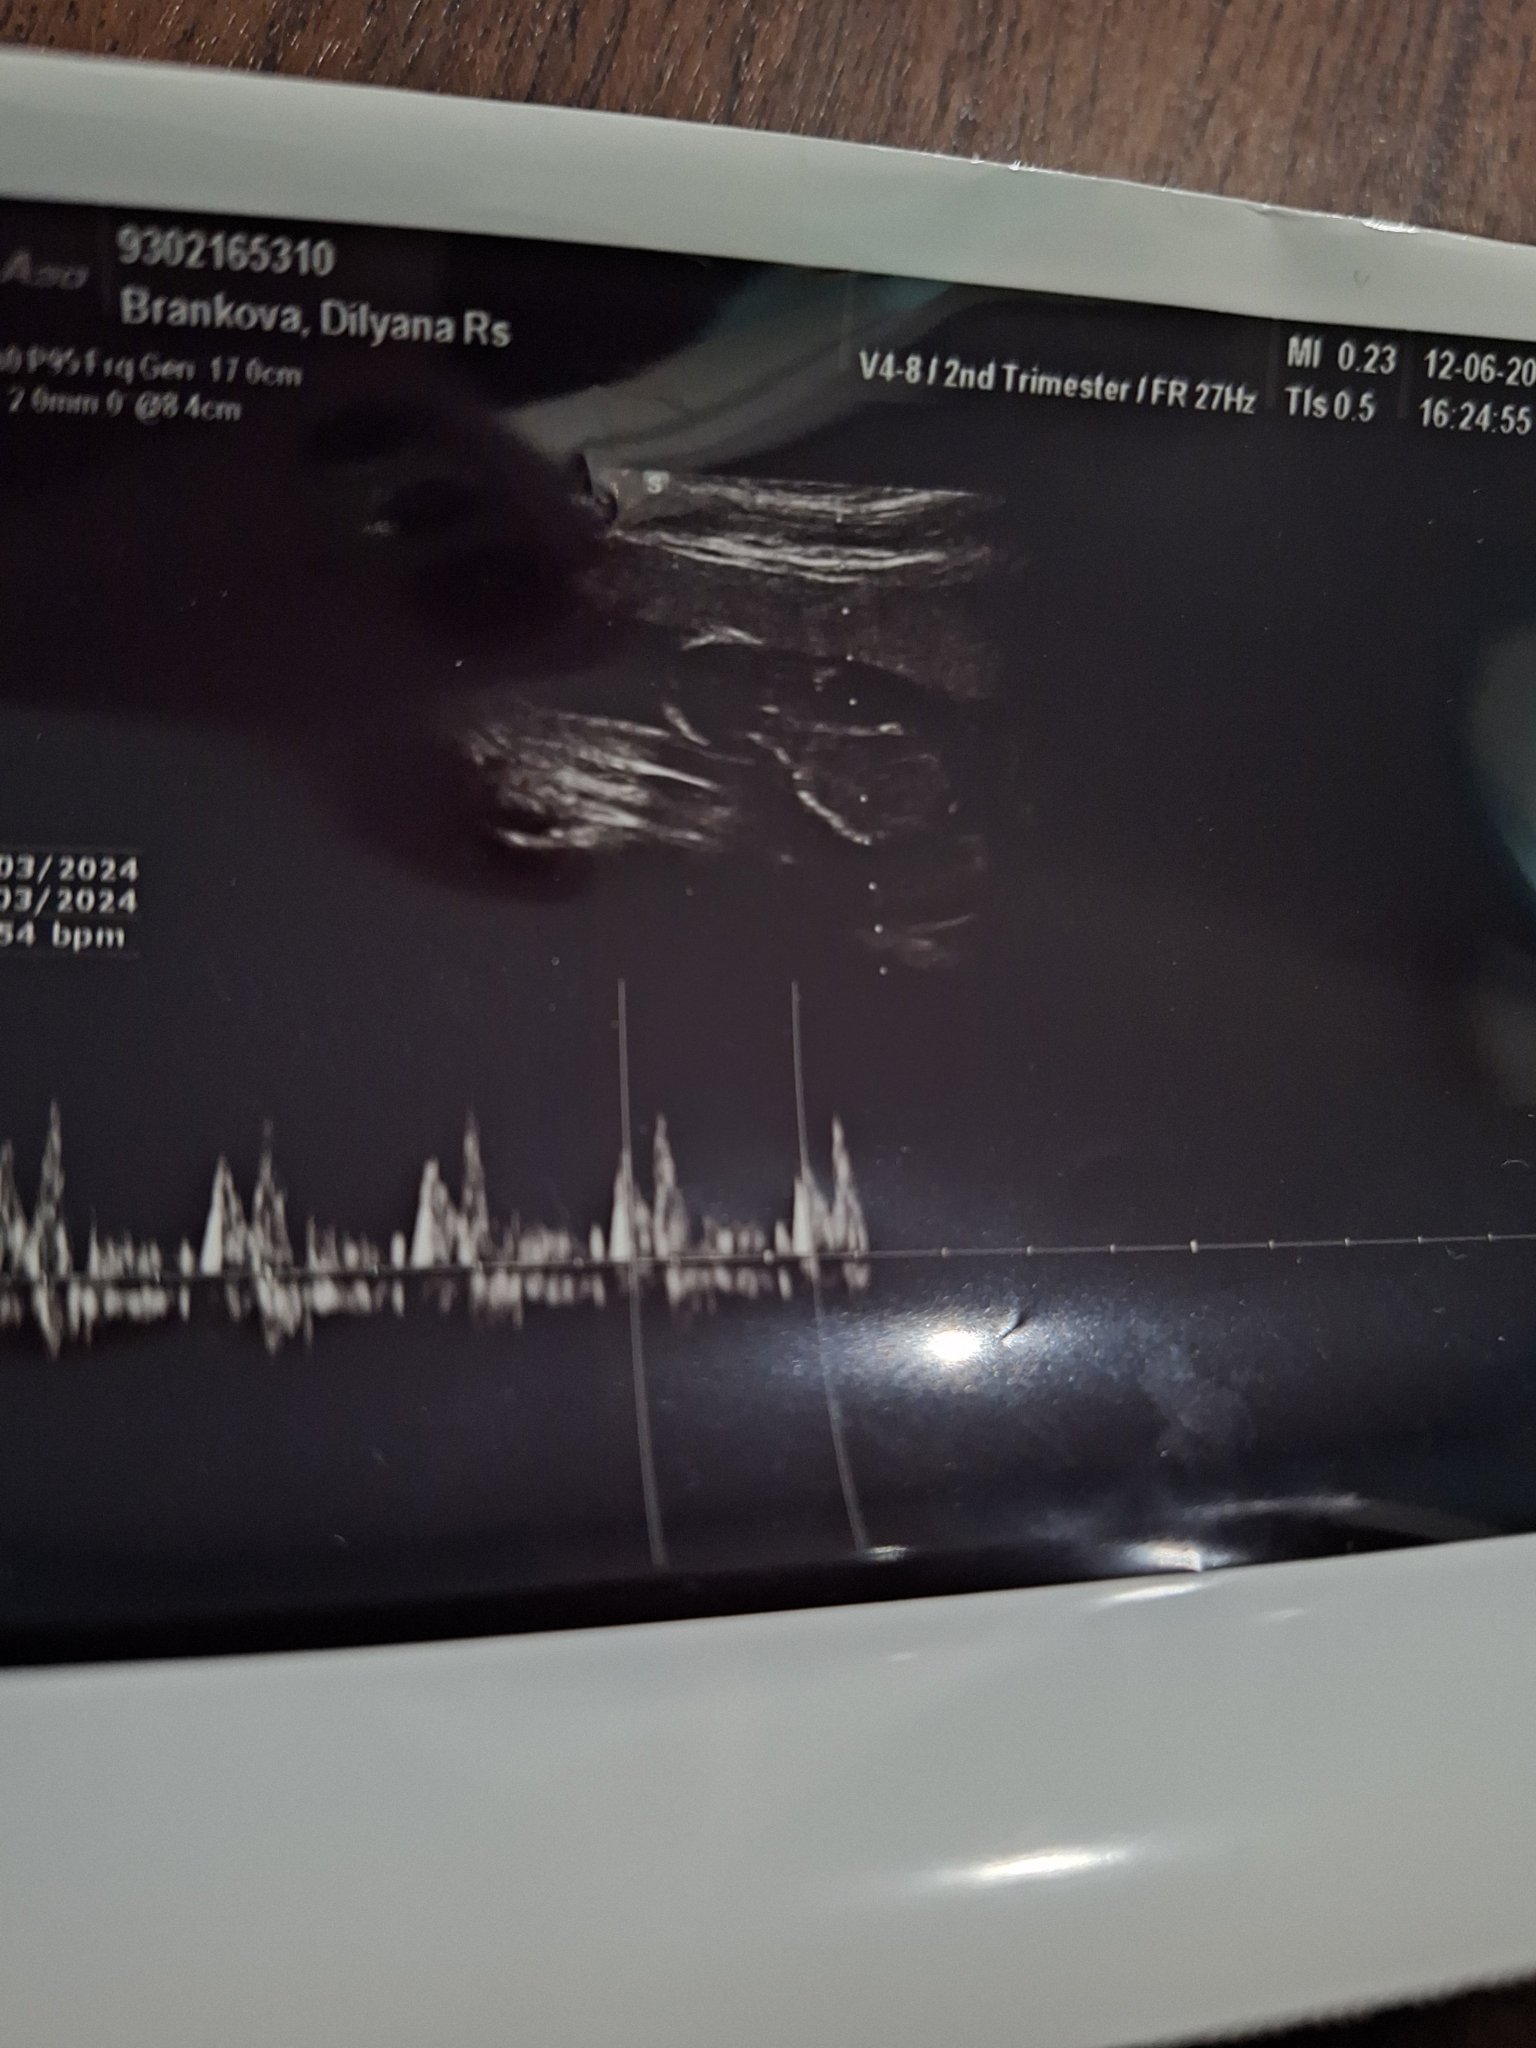

Маменца, днес бяхме на преглед. В 14г.с. сме. Всичко с беба е супер слава Богу. Пуснахме микробиология и цитонамазка, утре ще пусна и кръв и урина. Аз вече съм официално болничен и си почиваме вкъщи. Нямам оплаквания, освен придърпване от време на време. С предна плацента е и явно ще се усетим по-късничко, вече нямам търпение Grinning